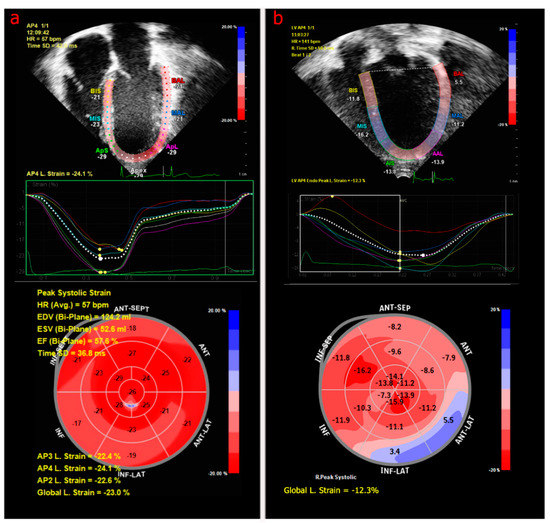

In addition to measuring systolic and diastolic function, screening for cardiomyopathy must also include an assessment of cardiac muscle architecture and deformation [48]. This can be measured as myocardial strain (MS) by 2D echocardiography via Tissue Doppler Imaging (TDI), which measures tissue velocity to quantify myocardial motion [47,49], or by speckle tracking software, which reflects a spatial gradient of local velocities, measuring local compression and expansion rates not affected by overall heart motion. MS is less dependent on loading conditions than EF or FS [43,44,49] and thus may better detect early cardiac toxicity. Deformation is measured in three dimensions, including: global longitudinal strain (GLS), which measures myocardial shortening from base to apex (Figure 1); global circumferential strain (GCS), which measures the systolic shortening of the short axis of the ventricle; and radial strain, which measures myocardial thickening from the endocardium to the epicardium [50]. Strain analysis in adult survivors of pediatric cancer demonstrated that only 5.8% of subjects in the cohort had reduced EF, but 32% had reduced GLS [44]. In addition to improved sensitivity, strain has shown evidence of its possible use as a predictive tool. Early reductions in GLS [51] and GCS [52], as measured from baseline to completion of treatment, may identify childhood cancer survivors at risk of the subsequent late development of cardiomyopathy.

Figure 1.

Apical four-chamber speckle-tracking images measuring left ventricular strain in asymptomatic pediatric patients who underwent chemotherapy with normal strain (a) and abnormal strain (b). In the middle panels, the colored lines correlate with 2D segments of the LV and the dotted line represents the average strain. The lower panel summarizes the global longitudinal strain in a bullseye plot, with blue representing dyskinetic segments in patient (b) with abnormal strain.